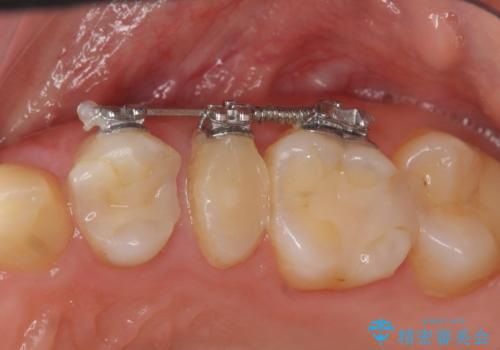

- 部分ワイヤー矯正

- 50.6万円(ジルコニアクラウン×3・仮歯×3・部分矯正)費用は治療当時の料金となります

当初、歯ぐきよりも深い虫歯のぞんざいや、歯のポジションに問題がありましたがマルチブラケットを用いた部分矯正を行うことで適切な位置へと歯を移動させ、歯周環境を整えたセラミック治療を行うことができました。